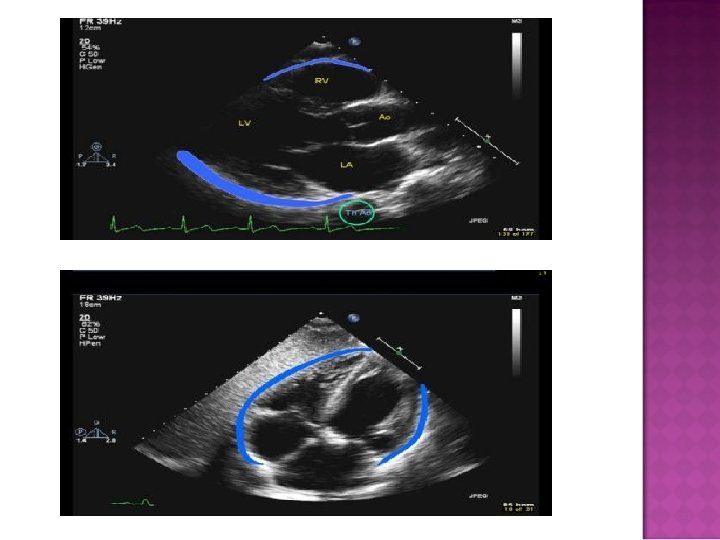

M-Mode

M-mode Cannot determine volume of accumulated fluid accurately

Pressure in pericardium exceeds s Compressive effect in intrachamber Diagnostic techniques 2 D looking for RA/RV collapse during diastole M-mode for RA/RV collapse during diastole Doppler of Mitral and Tricuspid inflow Mitral inflow to decrease by 25% with inspiration Tricuspid inflow increased by 40% with inspiration IVC diameter fails to increase with inspiration